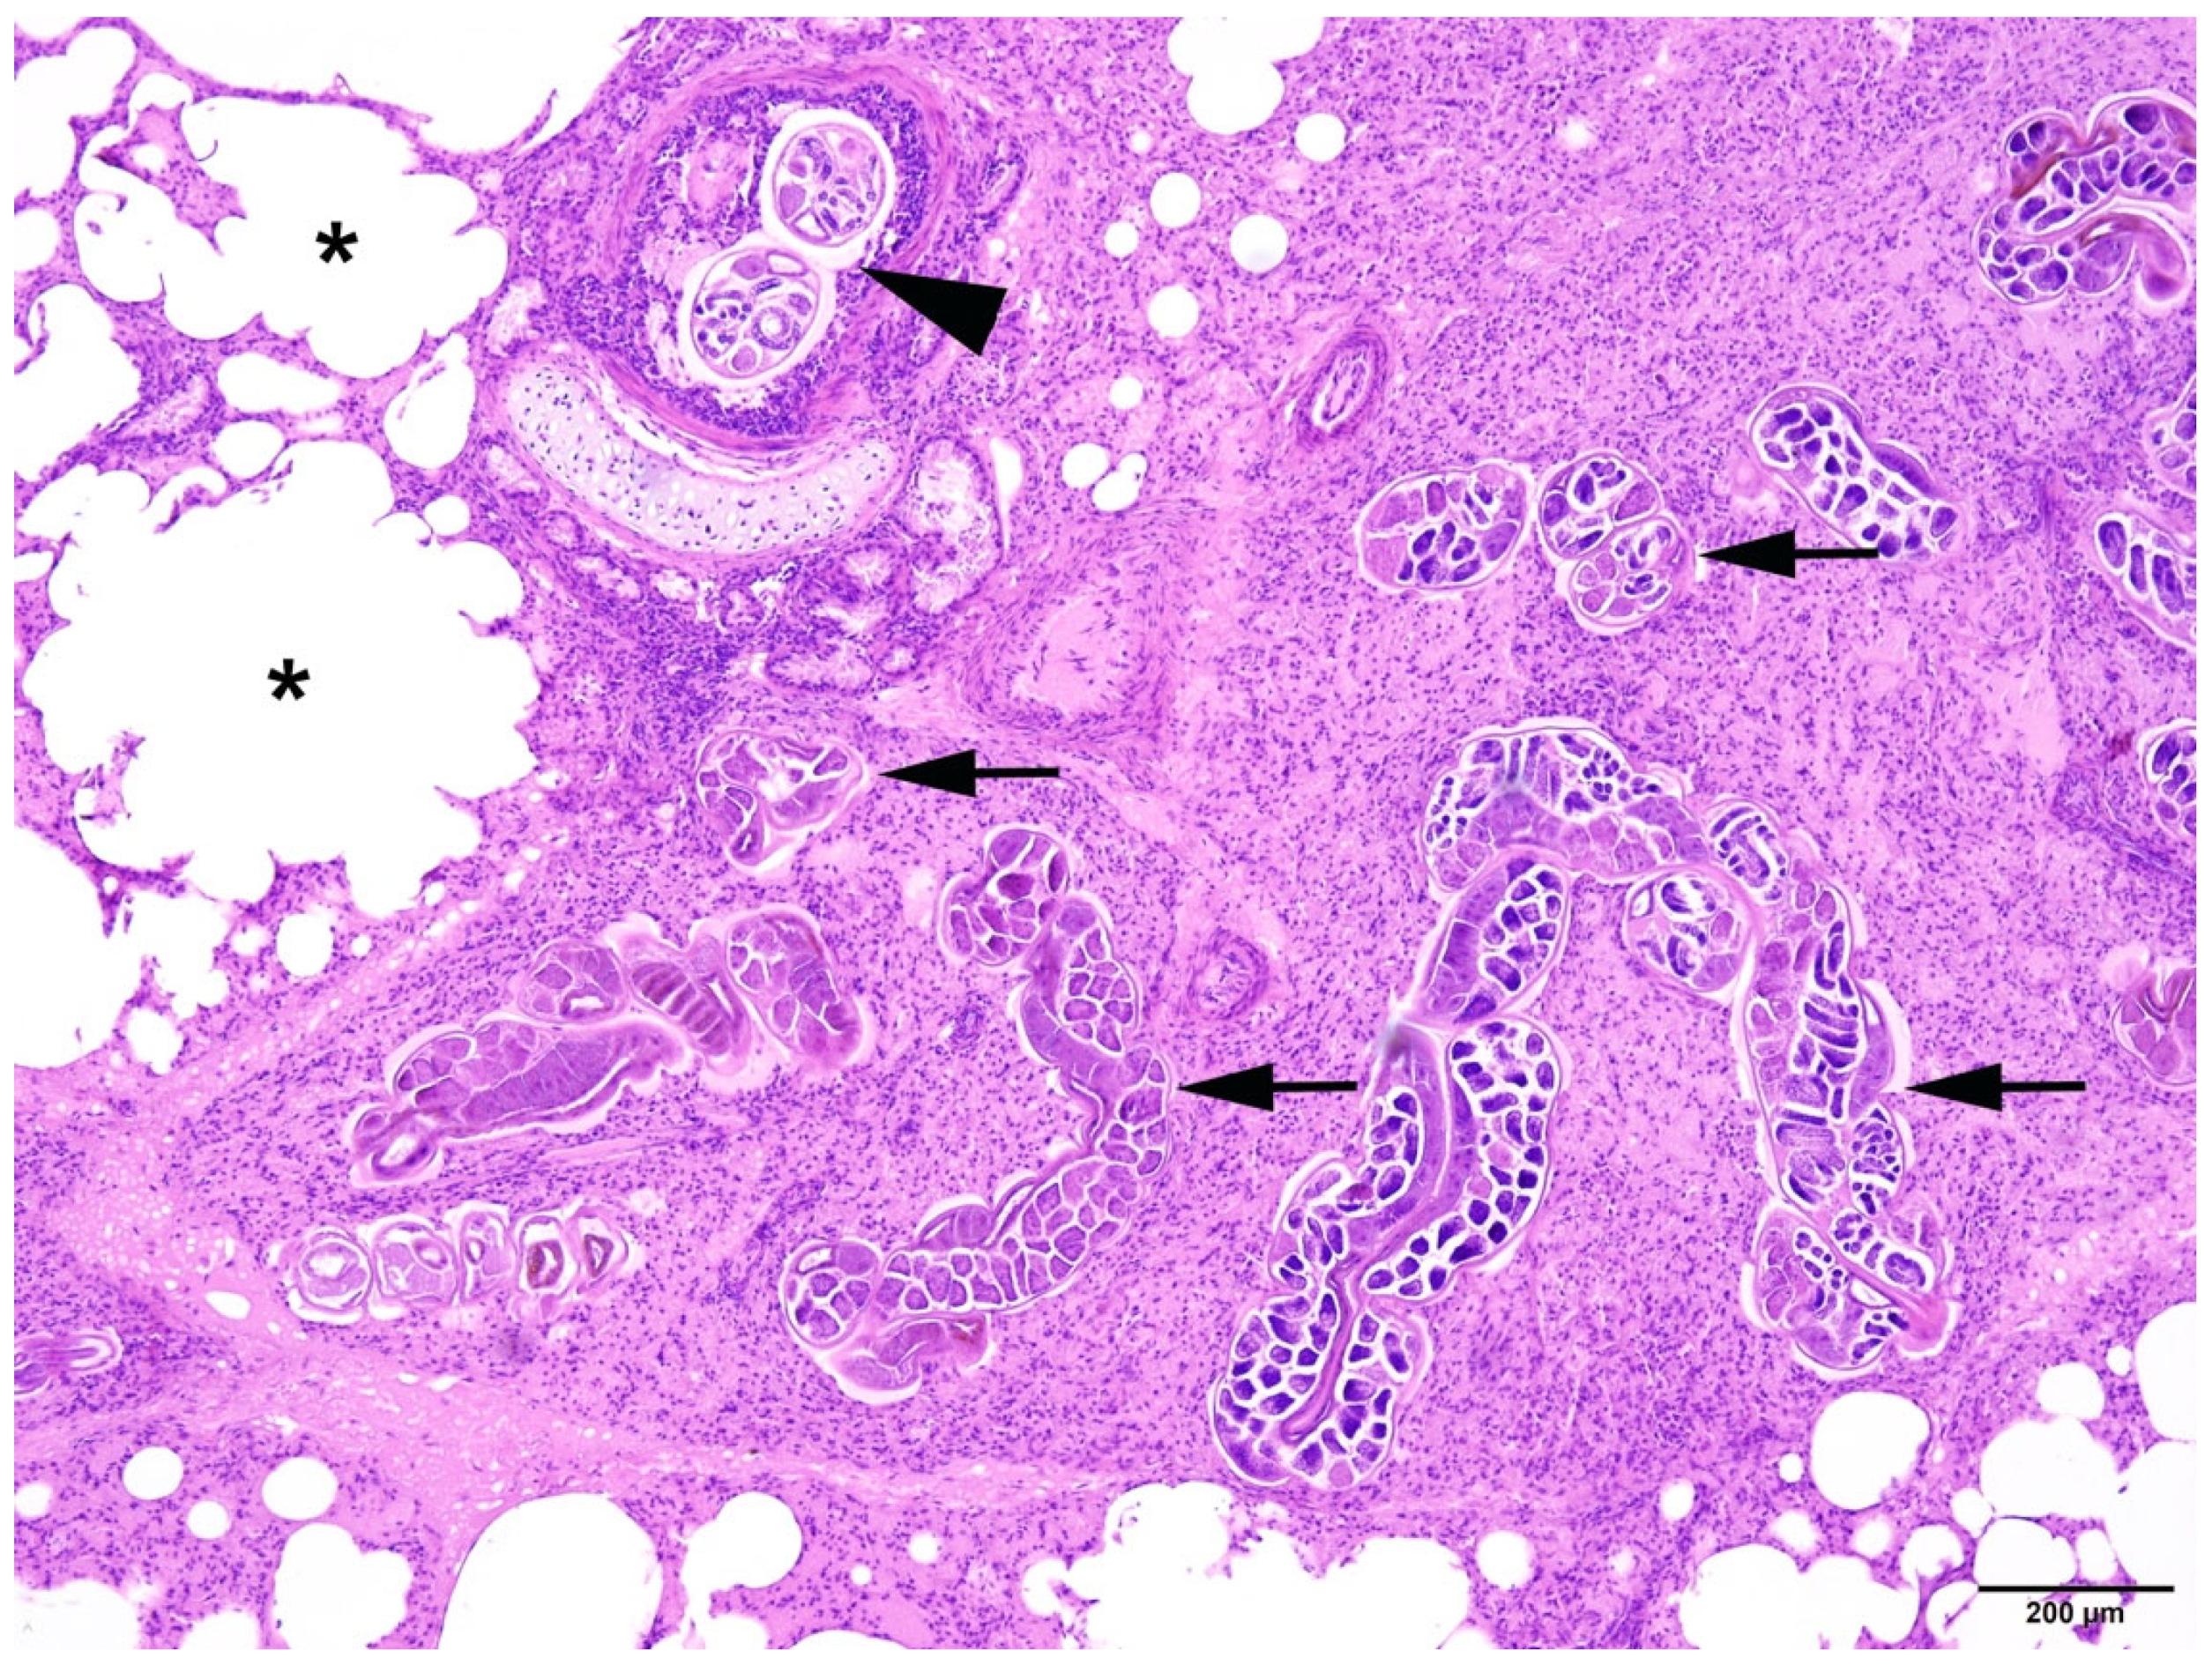

Different severity grades of alveolar/interstitial pulmonary emphysema (pathological accumulation of gas in the alveoli and/or cell spaces) could be detected in 44 animals often associated with parasitic infection and bronchopneumonia (Figure 9). Pulmonary atelectasis (collapse of alveoli) was found in 21 individuals. In 46 animals, alveolar/interstitial pulmonary oedema (pathological fluid accumulation in the alveoli and/or cell spaces) was recorded, with alveolar oedema present in 37 animals.

Figure 9.

Harbour seal, lung: severe pulmonary endoparasitosis with nematodes in a bronchus (arrowhead) and in the parenchyma (arrows) with associated atelectasis. Adjacent pulmonary tissue displays alveolar emphysema (asterisks). HE (4×).

In 29 examined seals (42%), a nematode infection was observed in the bronchial tree (Figure 5). The majority of respiratory parasitic infections were recorded in the younger individuals (age class I, n = 22), while no cases were recorded in the older animals (age class III). Respiratory parasitosis ranged in terms of severity presentation (mild to severe). Two animals in the age classes I and II presented minor parasitic infections, seven had moderate parasitic infections, and the majority (n = 20) displayed severe parasitic infections in the respiratory system. This finding was particularly evident in animals of age class I (n = 16) which simultaneously presented good nutritional status. Parasites retrieved from the trachea (Figure 5), large main bronchi and smaller pulmonary bronchi were identified as roundworms Otostrongylus circumlitus. The largest nematodes (Figure 6) were up to 14.5 cm long (average) and had a diameter of 2 mm (unfixed). Often, lungworms were also isolated from the larynx and stomach.

In all animals with respiratory parasitic infections, bronchopneumonia or pneumonia was detected. Several types of inflammation could be diagnosed, including catarrhal-purulent or -haemorrhagic, granulomatous-necrotising, purulent-necrotising, and alveolar-interstitial. In most cases, pathological changes included several types of inflammatory lesions within the same animals (Figure 7 and Figure 8).